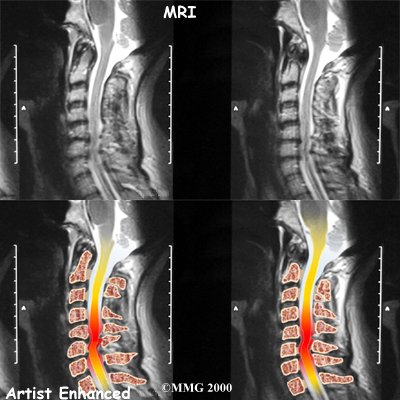

MRI

The magnetic resonance imaging (MRI) scan uses magnetic waves to create pictures of the cervical spine in slices. The MRI scan shows the cervical spine bones, as well as the soft tissue structures such as the discs, joints, and nerves.

MRI scans are painless and don't require needles or dye. The MRI scan has become the most common test to look at the cervical spine after X-rays have been taken.